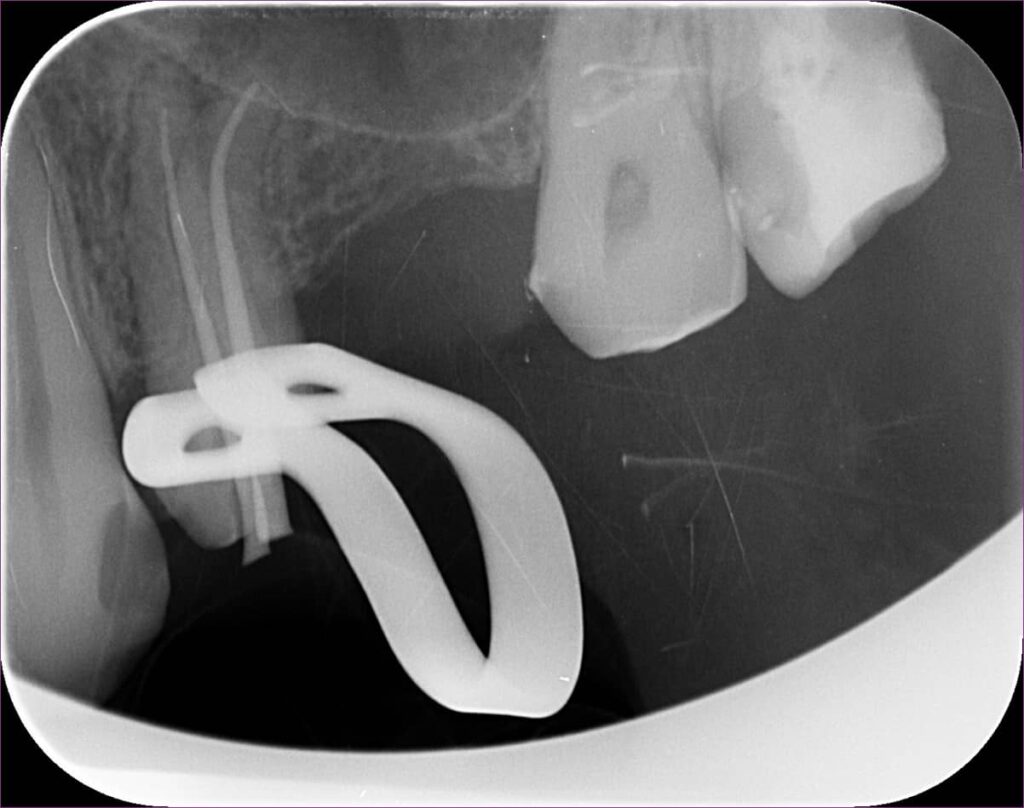

A fog kinyitása után a csatornákat a látható görbület miatt óvatosan, különleges technikával dolgoztuk fel. Már a kezelés elején érzékelhető volt, hogy a két, egyébként külön kijárattal rendelkező csatorna között van kapcsolat. Az egyik csatornába egy speciális szívóberendezést helyezve a másik csatornából is sikerült eltüntetni a folyadékot. Közvetlenül a gyökértömés előtt a majdani gyökértömő „pálcikákkal” készült röntgenfelvételen ellenőriztük, valóban jó helyen vagyunk-e, és az elektromos bemérő készülékünk segítségével jó hosszokat sikerült-e megállapítanunk. A felvételen egyenesebbnek látszó gyökérben rövidebbnek tűnik a hossz a röntgenen látható véghez képest, azonban itt nem a gyökércsúcson van a kijárat, hanem a gyökér oldalán.